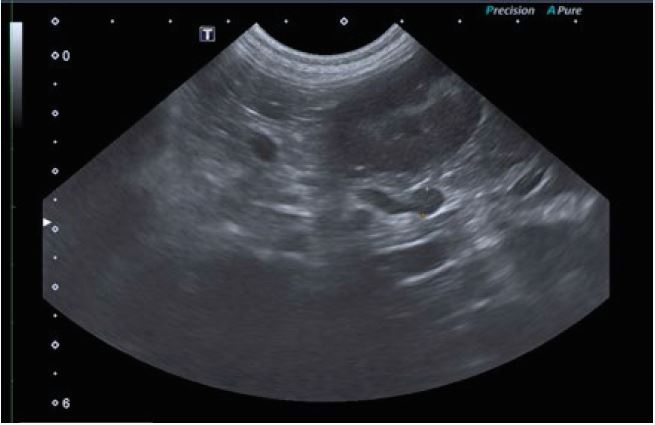

Огляд черевної порожнини собаки в 2D-режимі з

візуалізацією надниркових залоз.